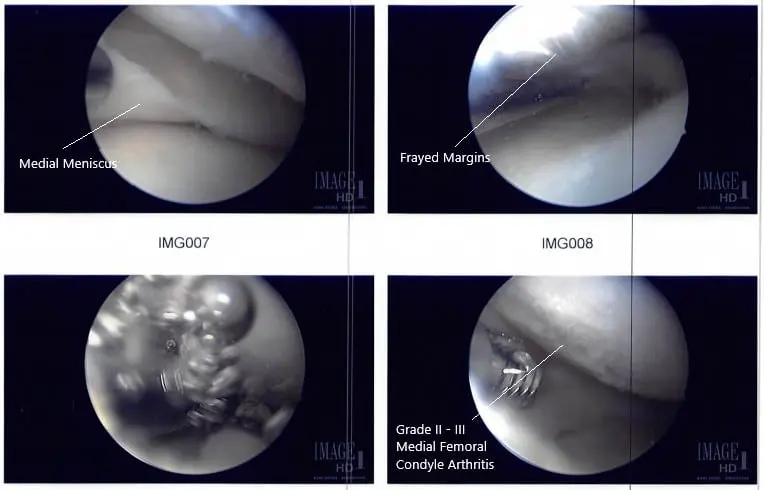

A lateral entry portal was made. The scope was entered and the knee was examined. There was patellofemoral arthritis. The scope was entered into the medial compartment. A medial entry portal was made using a spinal needle.

The medial meniscus was examined and found to have its margin fraying in the margin as well as degeneration of the inferior surface of the posterior horn of the medial meniscus.

The shaver was used to remove all the fraying and balance the meniscus. The scope was entered into the intertrochlear notch, where ACL was found to be intact. The scope was introduced into the lateral compartment, where lateral meniscus was also found to be intact. There was stage II to stage III arthritis of the medial femoral condyle, which was cleaned using a shaver. There was no chondral damage to the lateral femoral condyle.

Intraoperative arthroscope images.